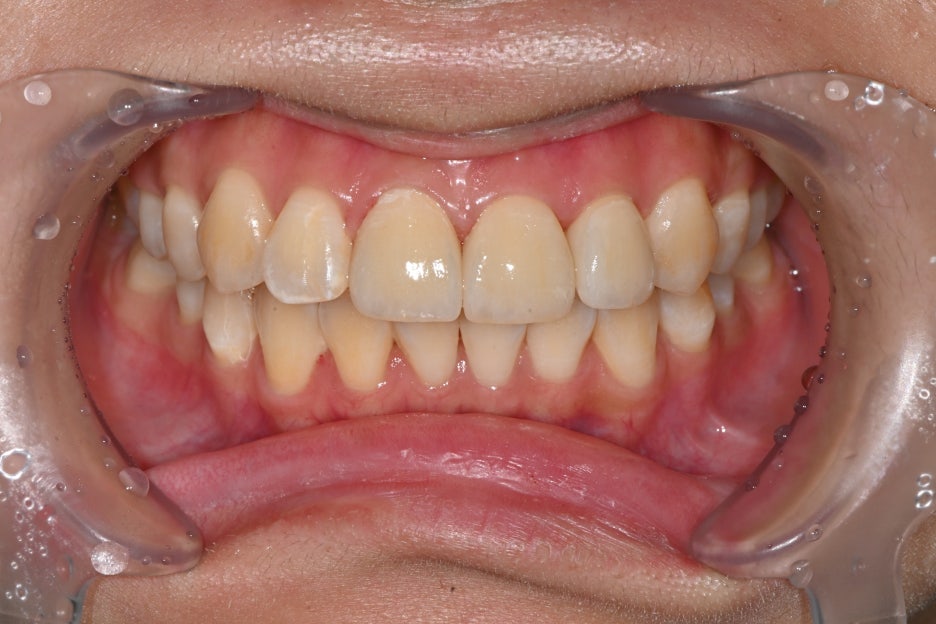

Before and after treatment photos

Photos before and after treatment

After treatment, the patient said,

“Now my front teeth are aligned again, so I feel more confident when smiling,”

and expressed satisfaction.

She also felt more reassured because people around her said it looked natural.